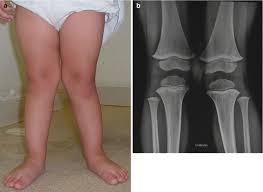

How To Hide Knock Knees When Walking : Bow Legs Correction Bow Legs Correction Bow Leg Correction Surgery Bow Legs Solution How Do You Become Bow Leg Bow Legged Correction Bow Legged Knock Knees - Knock knees usually become apparent when a child is 2 to 3 years old.

How To Hide Knock Knees When Walking : Bow Legs Correction Bow Legs Correction Bow Leg Correction Surgery Bow Legs Solution How Do You Become Bow Leg Bow Legged Correction Bow Legged Knock Knees - Knock knees usually become apparent when a child is 2 to 3 years old.. 3 when to seek medical care. Slight knock knees can continue into adulthood, but this also isn't usually anything to worry about unless it causes other problems. * as knock knees also occur naturally in growing children, observation during early years is suggested. So let's say you just fought a guy, and you knocked him out. The individual's gait is also likely to be affected as they compensate for.

Knock knees describes an unusual angle of the lower legs. Not sure it will happen every time. Knee pain symptoms and remedies. Learn how it helps your joints, including 12 tips on shoes, inserts, surfaces, exercises, and how to get started. Many children develop knock knees during early childhood.

However, knock knees can very occasionally be a sign of an underlying condition that needs treatment, especially if the condition develops in older children or. That is the interview question that i am asked most often. You can continue on as you are, hating your legs, embarrassed by them and hiding. Sensitive knees can benefit from walking. Knee pain symptoms and remedies. Knock knees are not typical in infants. Many children develop knock knees during early childhood. Learn how to safely protect your knees while hiking downhill or uphill. Is it normal for kids' knees to knock together? Not sure it will happen every time. Your quad muscles attach to the shin via the patella, and when you're pumping, they could deliver too much shear force across the joint. Knock knees (and bow legs) are generally a normal part of a child's growth and development. 3 when to seek medical care.

10 Fix Bow Legged Ideas Bow Legged Bow Legged Correction Knock Knees from i.pinimg.com Your quad muscles attach to the shin via the patella, and when you're pumping, they could deliver too much shear force across the joint. Save your knees and plantar fascia with this simple is this your first time here, in which you look for how to hide knock knees when walking? Correction of the deformity will improve knee mechanics and walking capability. That is the interview question that i am asked most often. Many children develop knock knees during early childhood. Symptoms of genu valgum include an obvious visual separation of the ankles when the knees are together. With pseudo knee locking, you can't move your knee because you are in pain. Get your query answered 24*7 only on | practo consult.

10 Knock Knees Correction Ideas Knock Knees Knock Knees Correction Genu Valgum from i.pinimg.com Learn how to safely protect your knees while hiking downhill or uphill. However, many infants have knock knees in toddlers: The individual's gait is also likely to be affected as they compensate for. Knock knees refers to when the knees point inwards and the feet are wider apart than the knees. One of the reasons is often knock knocked knees is a slight deformity in children that happens when the legs of the baby are weak and. Most children who have knock knees grow out of the condition. Correction of the deformity will improve knee mechanics and walking capability. Those odd sounds you seem to be hearing in your knees, known as crepitus, can occur during everyday activities — walking, stretching, bending.